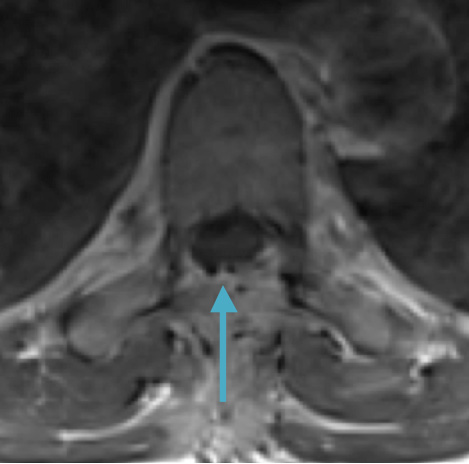

Postoperative MRI T2 illustrating the restoration of CSF surrounding the cord (blue arrow)

Pathology came back as Atypical Meningioma, WHO grade 2. Postoperative MRI showed a gross total resection without residual tumor, and appropriate spinal cord re-expansion. On her most recent follow-up at 6 weeks, she was very pleased with the results from the surgery. She reports resolution of her preoperative thoracic back and radicular pain, and great improvement with her ability to ambulate and overall function. It is demonstrated by her interval VAS of 2/10, and ODI of 23/100. She is expected to continue improving with time and therapy. Follow-up plan is to observe with radiographic surveillance.

Postoperative MRI T1w demonstrating interval resection with cord re-expansion (blue arrow)